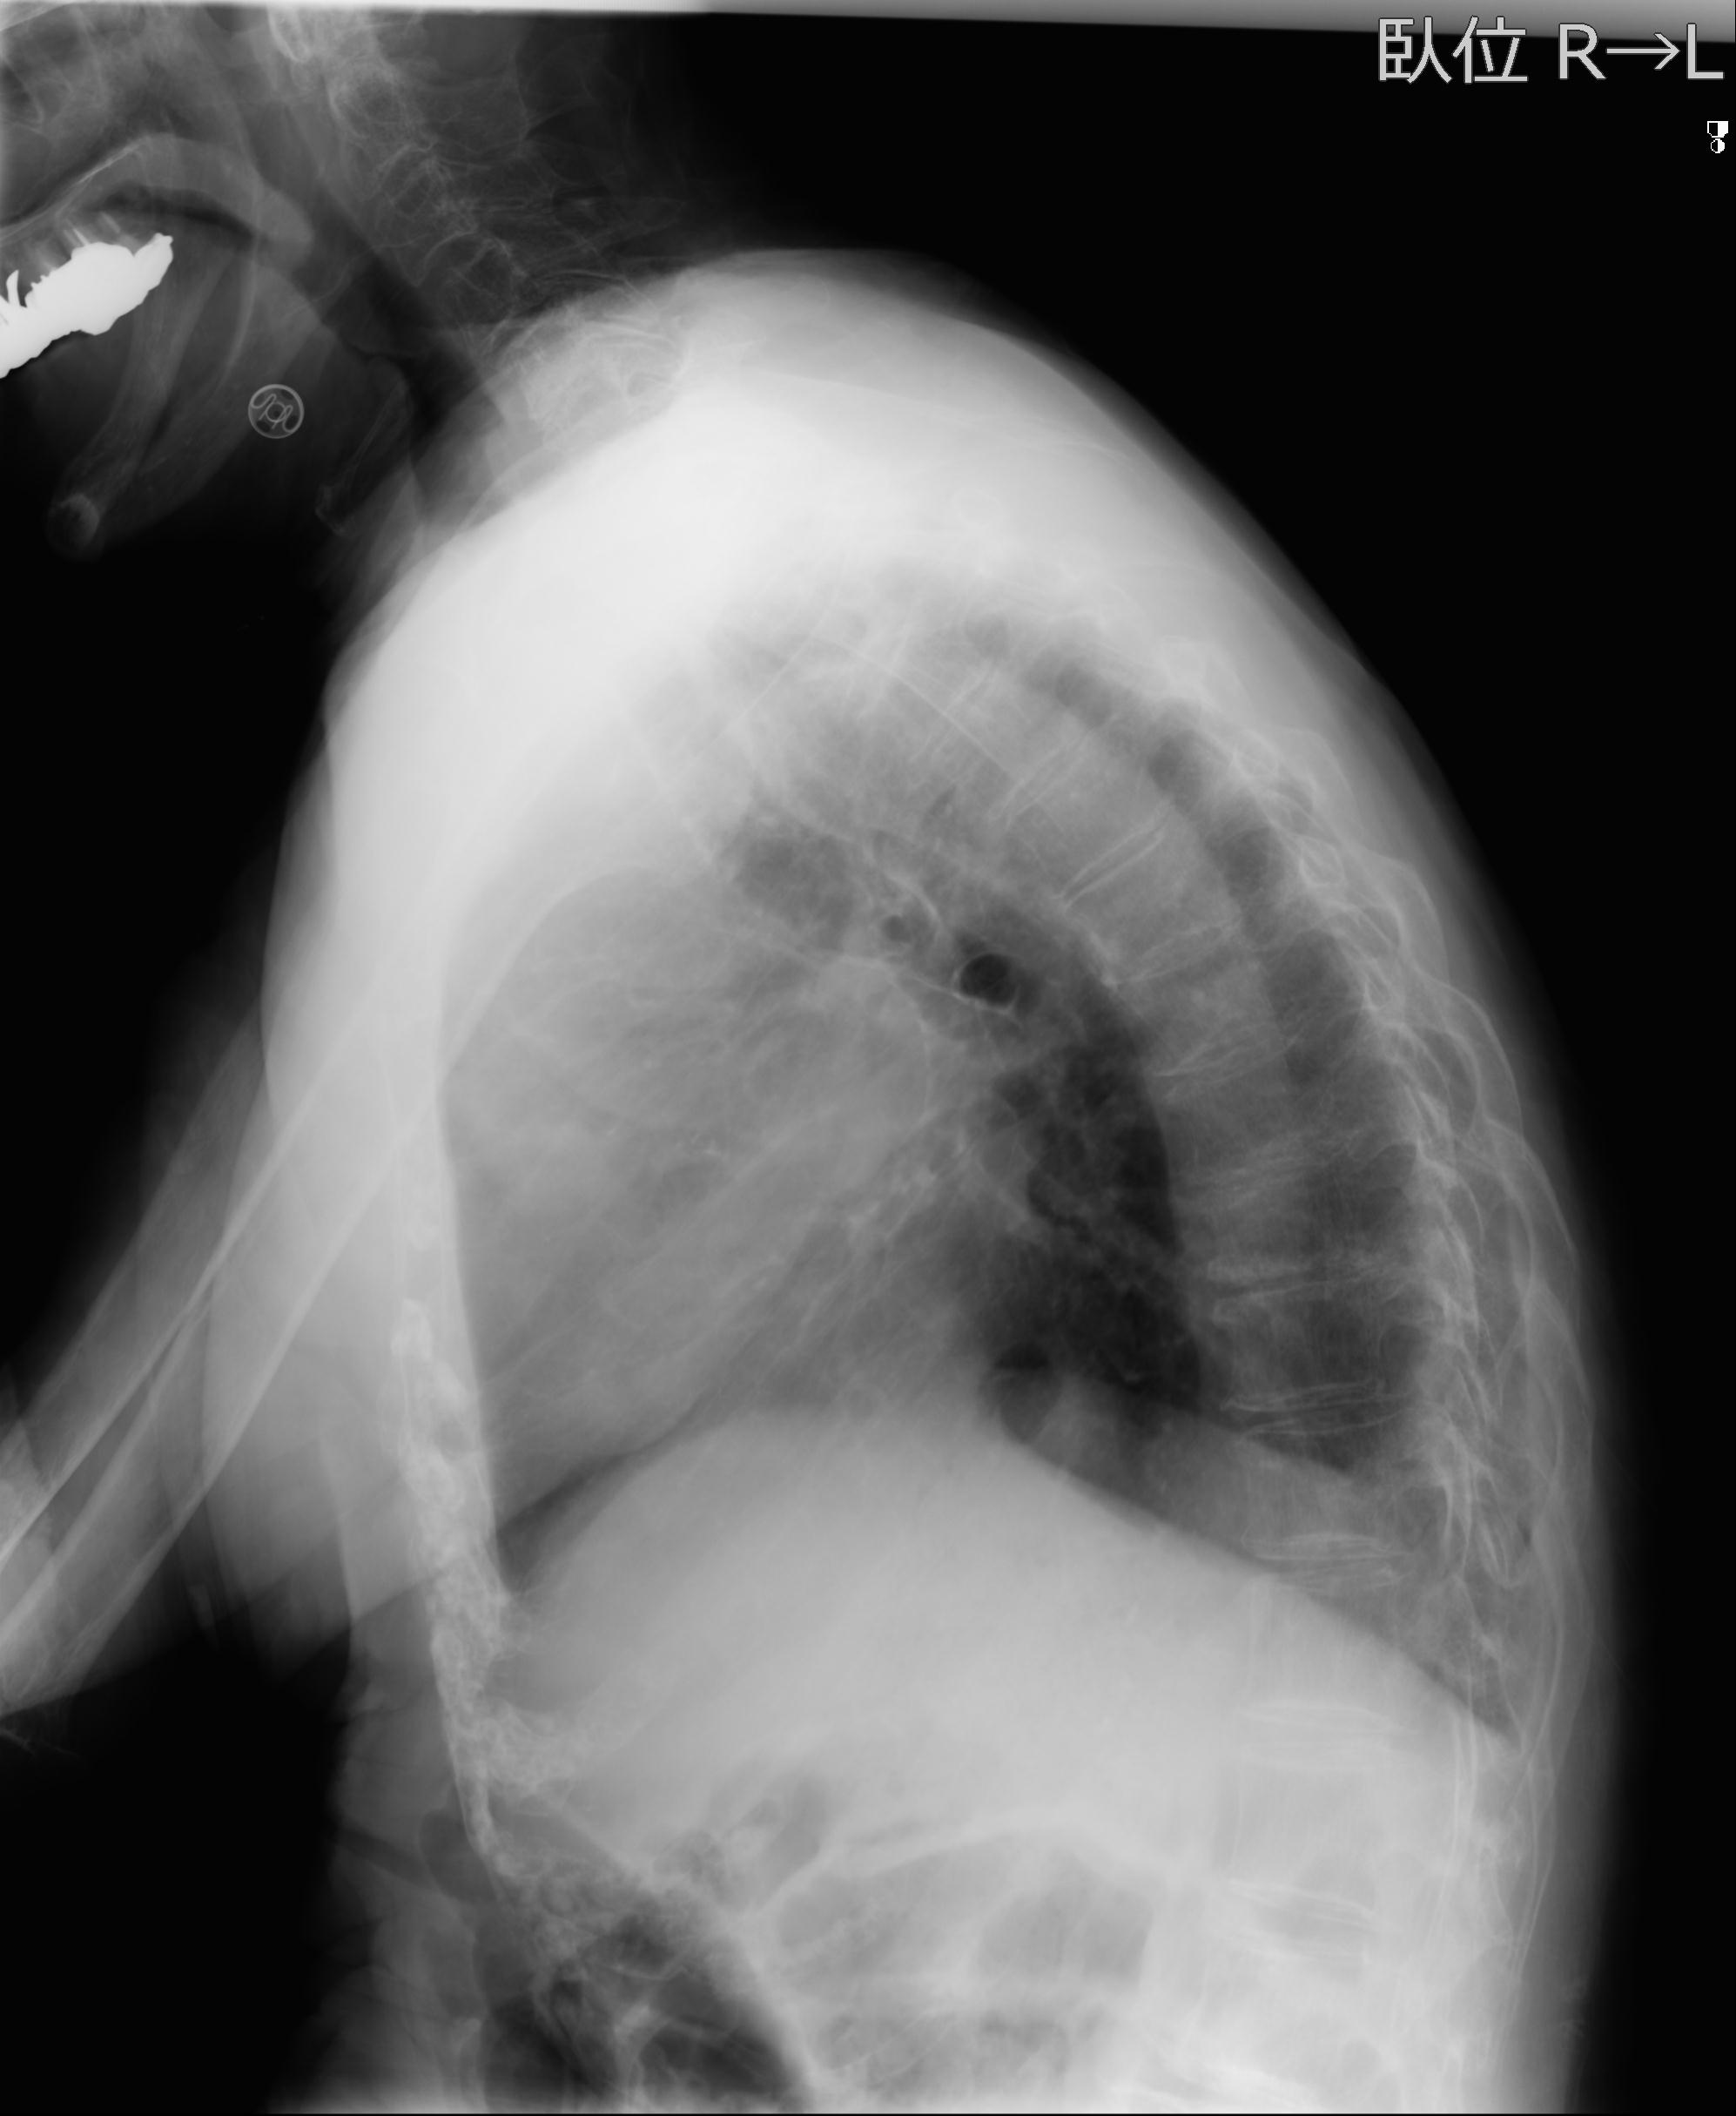

56476 8/28 4R 1/21 2R 左足関節 デジカメ写真 72歳女性 右足関節AS